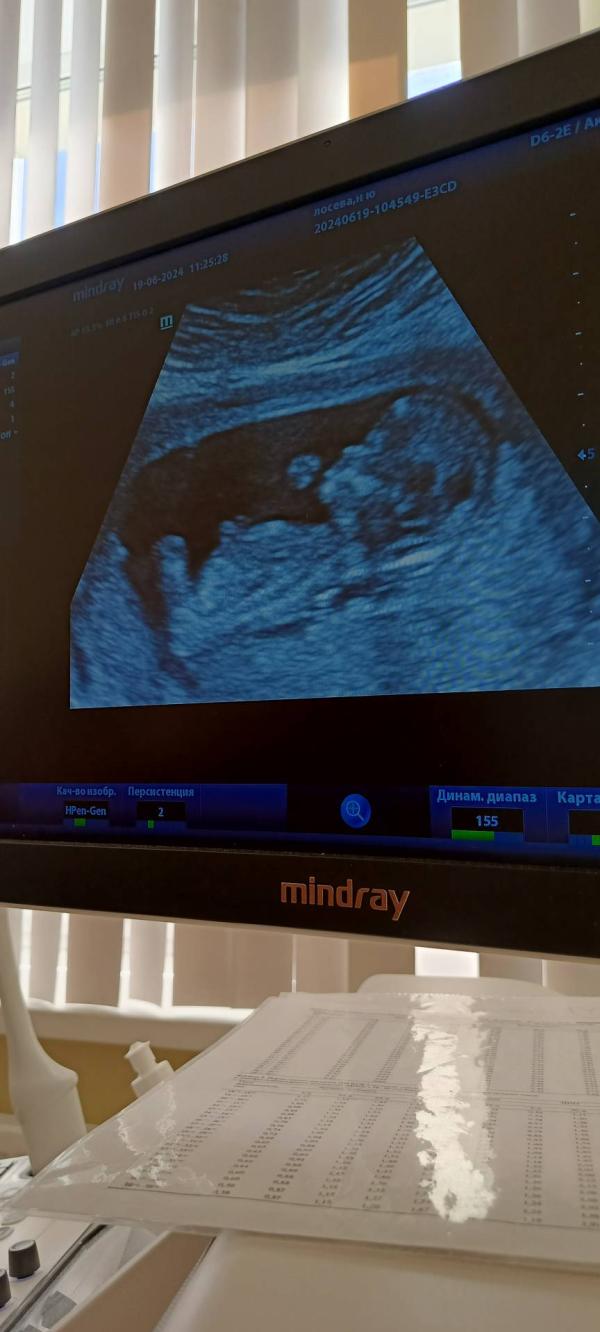

Сегодня была на первом скрининге, предварительно у нас будет второй мальчишка😂. За 2 недели до... Я хотела купить скейч открытку, где узист напишет пол, и мы дома семьей сотрем, но я лоханулась и нечайно заказала с готовым полом, и там был мальчик 🤗. Думали конечно, что будет девчонка, ну братик тоже хорошо. Теперь думать над именем, я не особо люблю мужские имена

Сказали на 1 мальчик, в итоге девочка, с 17-18 недель точно только могут сказать

@ann_st, там еще нет пениса. Предполагают по расположению и направлению полового бугорка. Не более.